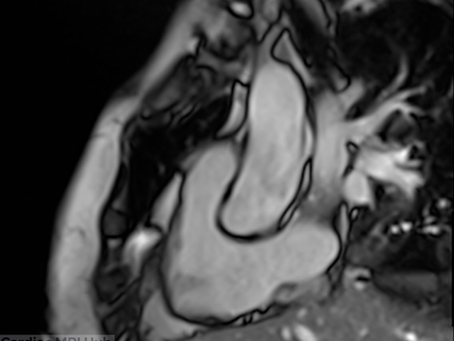

Understanding the Left Ventricle 3-Chamber View: Comprehensive Cardiac MRI Planning for Technologists

The left ventricle three-chamber (LV 3ch) view is a powerful diagnostic tool that uniquely visualizes the LV outflow tract, both mitral and aortic valves, and the relationship between the left ventricle and ascending aorta. Acquired after standard chamber views, this plane is essential for evaluating valvular disease, outflow obstruction, and basal myocardial segments. This guide provides expert techniques for precise 3ch planning and optimization. 3 Chamber Planning Left ven